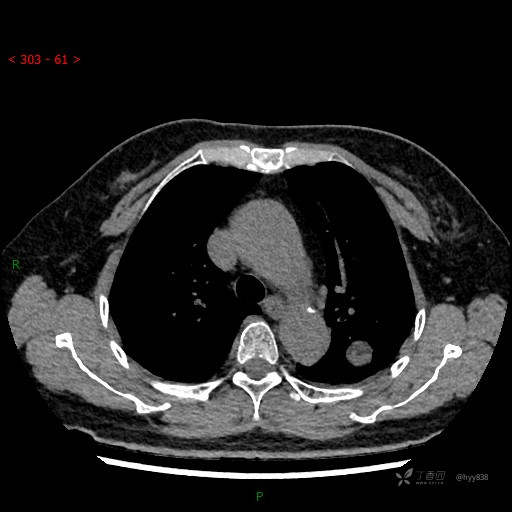

增强动脉期

各期CT值:28hu、58hu、69hu